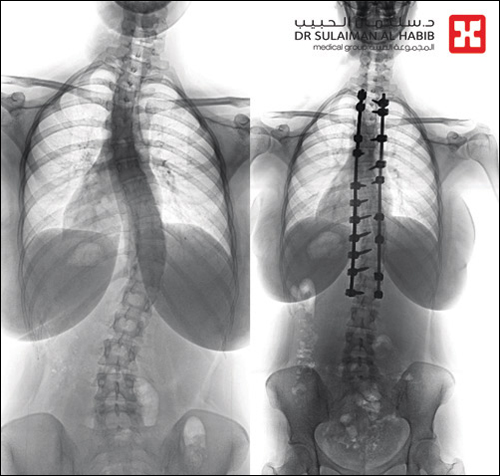

وقال د. خليفة إن المريضة راجعت المستشفى وهي تشتكي من انحناء جانبي للعمود الفقري منذ نحو سنة، ومؤخراً تزايدت حدة الأعراض، وأصبحت تعاني من صعوبة في ممارسة الحياة الطبيعة، وتغير نمط حياتها وتقيدت حركتها. وبينت الفحوصات الطبية التي أجريت لها في المستشفى إصابتها بحالة انحراف «جنف» بدرجة «43» بالفقرات الصدرية, وقد درس الفريق الطبي الحالة وخلص إلى ضرورة التدخل الجراحي لعلاج العيوب، والحد من المضاعفات. وقد أجرى الفريق عملية جراحية للمريضة تم فيها تقويم العمود الفقري بعدد «20» من البراغي والقضبان المعدنية والطعوم العظمية الصناعية، وتثبيت ودمج الفقرات، واستخدم الفريق في العملية التي استمرت لـ«4» ساعات جهاز الملاحة العصبية، إضافة الى مجموعة من أحدث الأجهزة الطبية التي ساهمت مع الكوادر الطبية عالية الكفاءة والتأهيل بالمستشفى في إنجاحها.

واستطرد د. الخليفة قائلاً إن المريضة بدأت في التحسن بشكل متسارع بعد خروجها من غرفة العمليات، واستطاعت المشي بعد أقل من «24» ساعة من العملية، بدعم وإشراف من فريق العلاج الطبيعي المتمرس، واستعادت قدرتها على الاستلقاء والنوم على ظهرها، فضلاً عن القوام والمظهر الطبيعي، بعد تعديل وضعية الحوض والكتف، كما أن طولها مع نجاح التعديل زاد بحدود «2» سم، وخرجت من المستشفى وهي بصحة جيدة، وتوقع أن تستعيد كامل صحتها سريعاً، بعد استكمال البرنامج العلاجي.